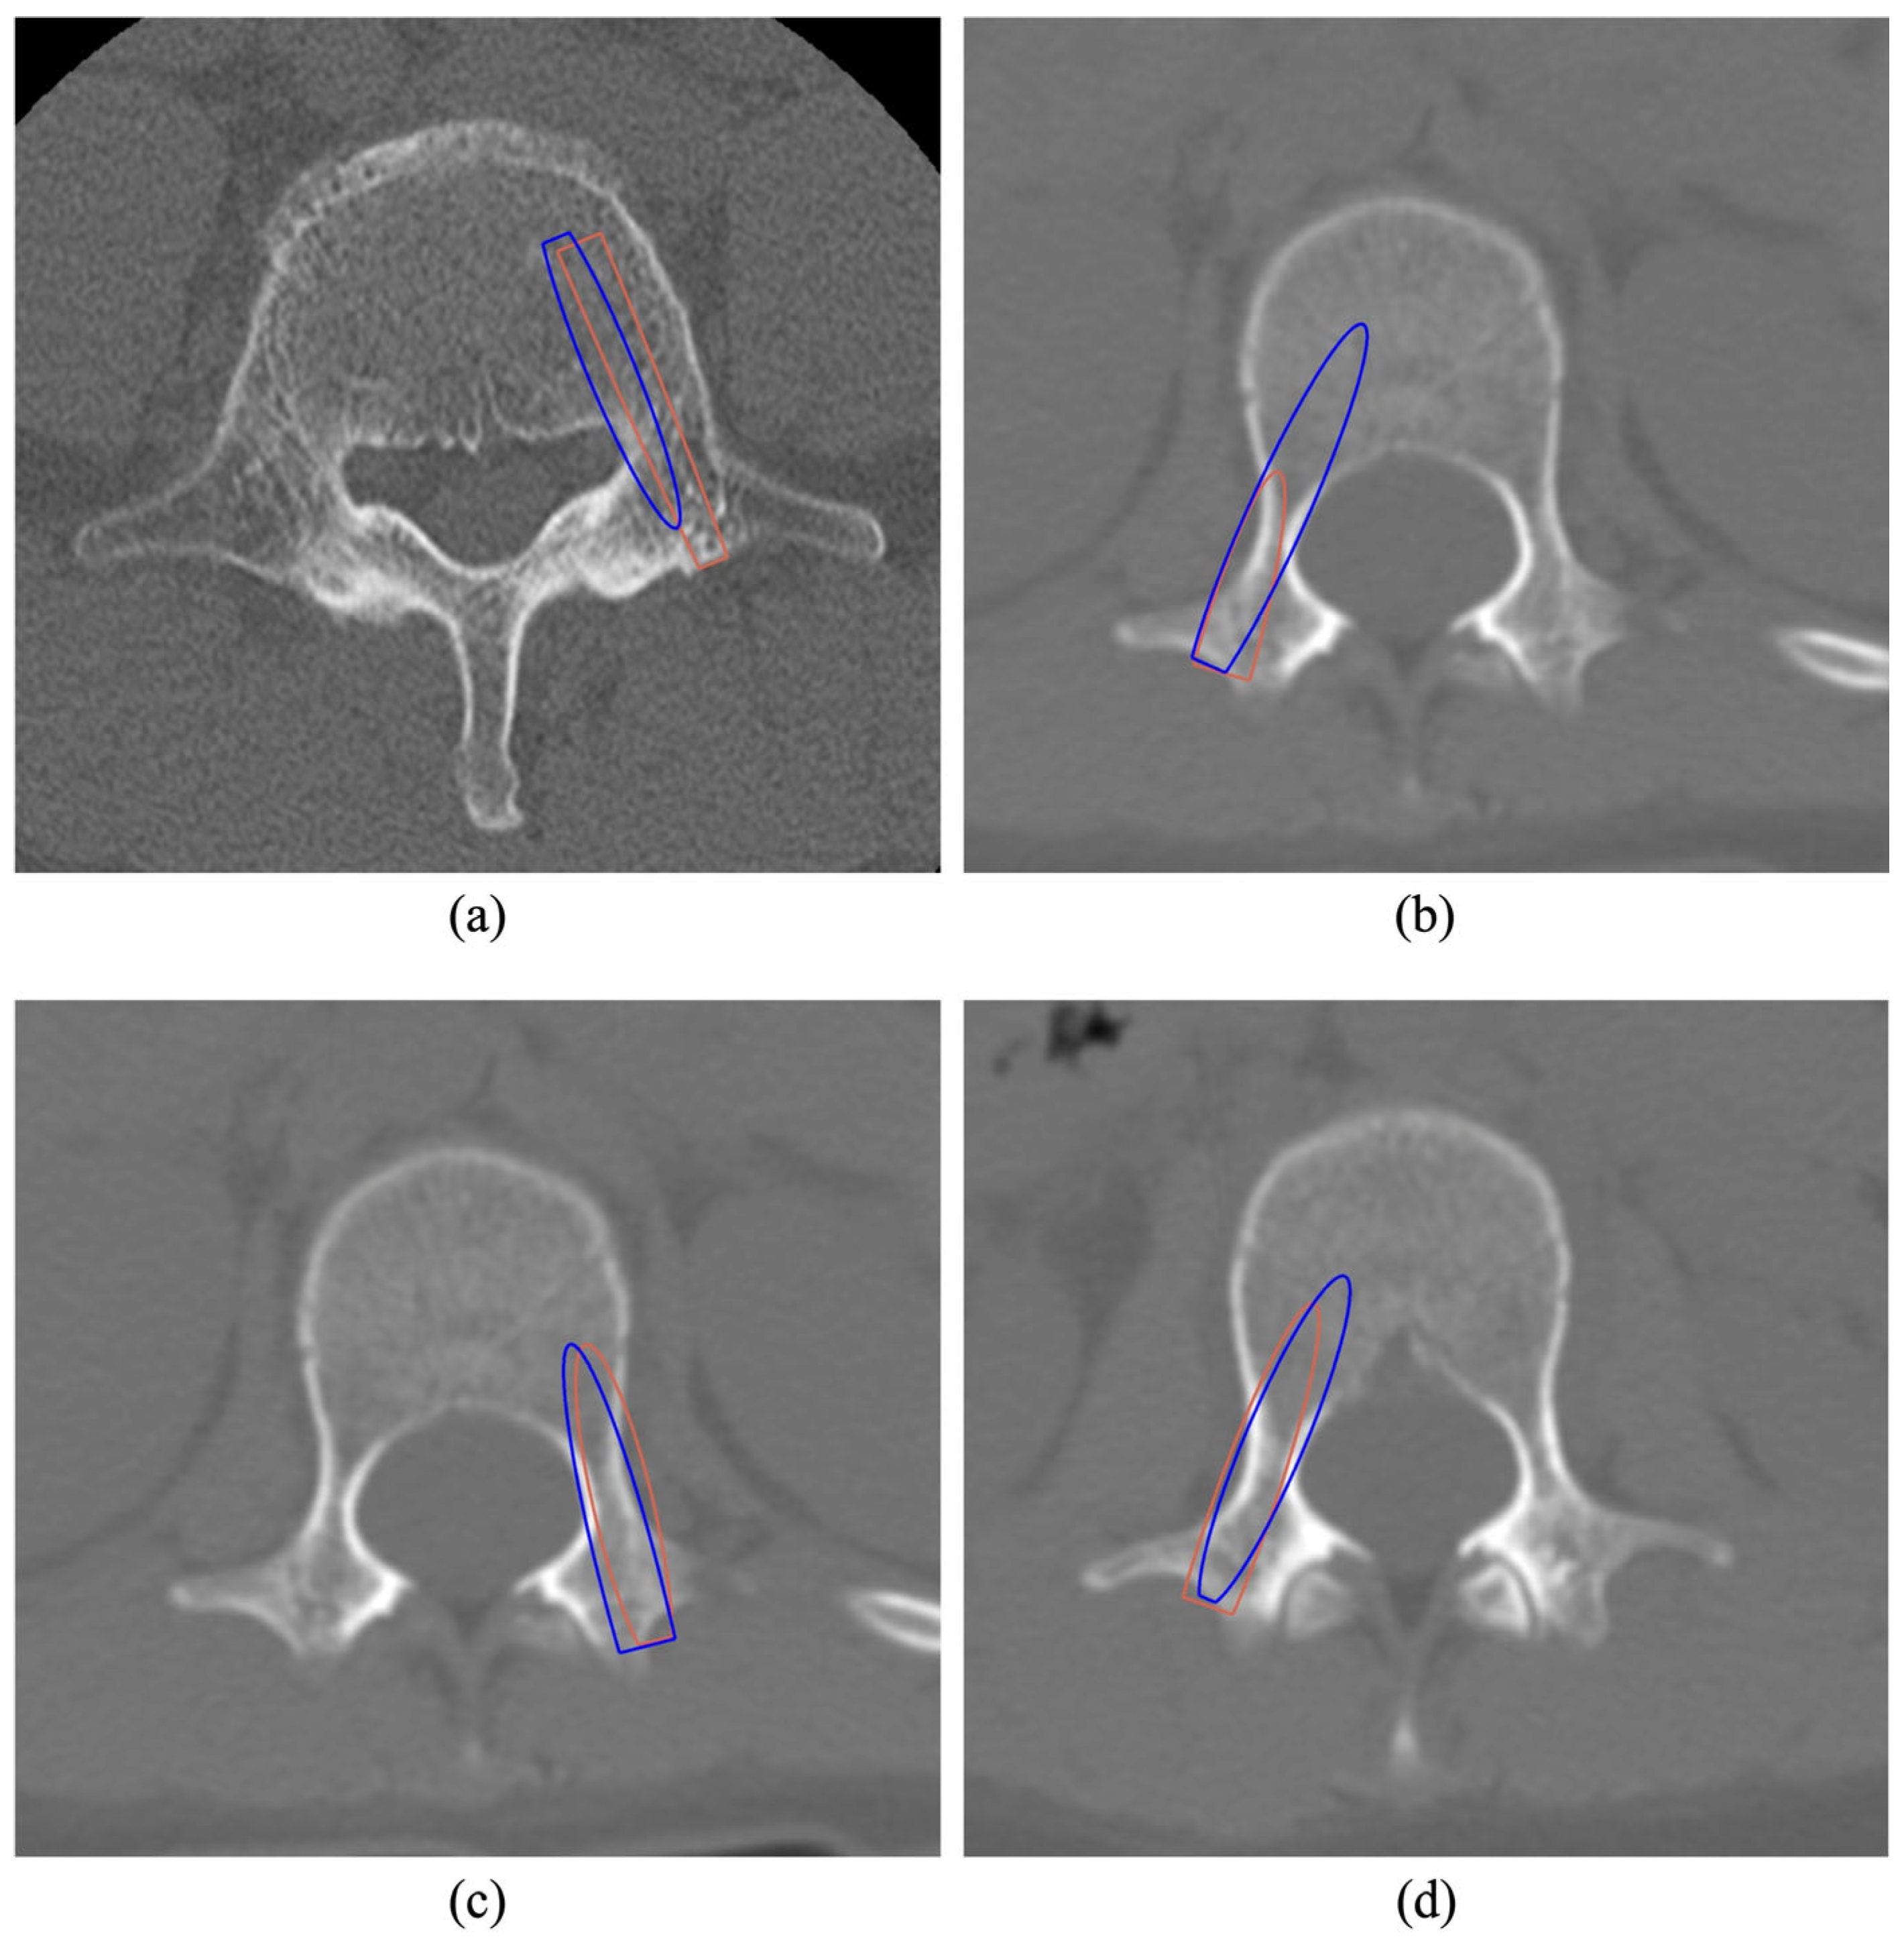

- Neural Network Architecture and Training: The neural network was created by modifying the standard PointNet architecture and was trained with a customized loss function to align the predicted trajectory with the ground-truth trajectory. The network’s output was then used to calculate entry and target points for screw insertion.

2.5. Evaluation

- Grade A: Intrapedicular insertion

- Grade B: Violation of <2 mm

- Grade C: Violation between 2 and 4 mm

- Grade D: Violation between 4 and 6 mm

- Grade E: Violation > 6 mm